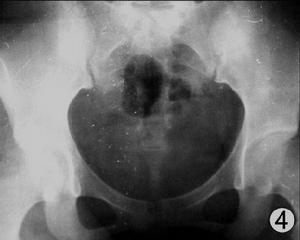

患感染性關節炎的兒童中有50%是年齡<2周歲者.在這些病例中,93%累及單側關節,尤其是下肢關節如膝關節(39%),髖關節(26%)和踝關節(13%).感染源有中耳炎,臍炎,中樞神經炎,股靜脈穿刺,腦膜炎和臨近的骨髓炎。

感染性關節炎非淋球菌性關節炎多由金黃色葡萄球菌(占45%),鏈球菌(占9%),及革蘭氏陰性菌如腸桿菌,綠膿桿菌(占40%),沙雷桿菌(占5%)引起.革蘭氏陰性菌感染多見於青年人和老年人,尤其是有嚴重創傷或嚴重內科疾病(如腎功能衰竭或腎移植,關節修復,SLE,RA,糖尿病,惡性疾病)和吸毒者.感染多原發於尿道或皮膚.80%的患者中,非淋球菌性關節炎見於單側關節(膝關節,髖關節,肩關節,腕關節,踝關節,肘關節).多關節細菌感染性關節炎患者常伴有慢性關節炎(RA,骨關節炎)或有一個經置換的關節.芽胞羅鏇桿菌是引起Lyme病的病原體,會引起急性遊走性關節痛並伴有發熱,頭痛,疲乏和皮膚損傷或間歇性單關節炎。

厭氧菌感染多數是單關節炎,易累及髖關節或膝關節(占50%).關節外的厭氧菌感染包括腹部生殖器,牙周膿腫,竇道炎,缺血性肢體炎症和褥瘡。